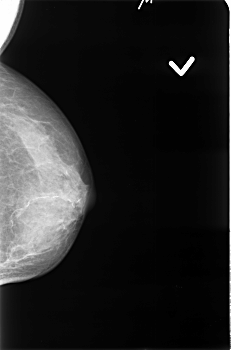

B_3396_1.LEFT_MLO

LEFT_MLO LINES 4512 PIXELS_PER_LINE 2968 BITS_PER_PIXEL 12 RESOLUTION 50 NON_OVERLAY